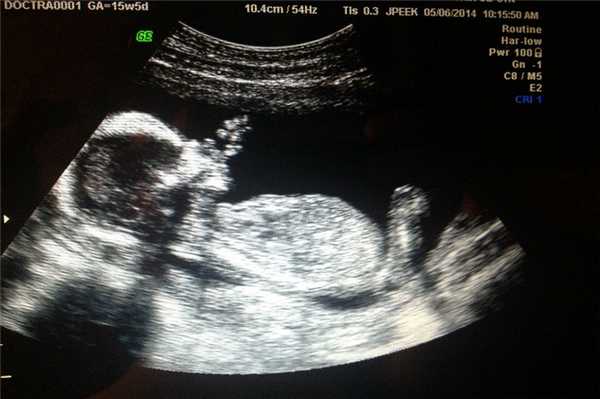

Фото УЗИ ребенка на 13 неделе беременности

Железы внутренней секреции к этому моменту почти полностью развиты и вырабатывают гормоны, в частности инсулин. Сердечно-сосудистая система малыша за сутки перекачивает больше 20 литров крови.

На мониторе прибора видны такие особенности развития:

- размер плода достигает 75 мм;

- части тела становятся более пропорциональными, но голова по-прежнему больше тела, а руки длиннее ног;

- лицо малыша меняется, глаза перемещаются ближе к центральной части;

- формируются мимические лицевые мышцы;

- движения конечностей беспорядочные и постоянные.

Фото УЗИ ребенка на 14 неделе беременности

К этому моменту уже сформированы основные внутренние органы, кости укрепляются, происходит доразвитие легких. Мочевыделительная система сформирована, в результате чего моча выводится непосредственно в околоплодную жидкость.

На фотографии ультразвуковой диагностики видны такие признаки:

- на лице ребенка появляются гримасы, выражение лица быстро меняется;

- формируются брови и ресницы;

- тело становится более пропорциональным;

- плод увеличивается до 80 мм;

- продолжается формирование наружных и внутренних половых органов.

Фото УЗИ ребенка на 15 неделе беременности

В этот период происходит активное развитие головного мозга и опорно-двигательного аппарата. Несмотря на то, что глаза малыша по-прежнему закрыты, он реагирует на свет.

На УЗИ размеры малыша достигают 10 см. Ребенок глотает амниотическую жидкость, может сосать пальчик за счет формирования сосательного рефлекса. Движения плода активные, но хаотичные.